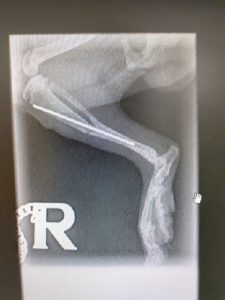

Two hogs have been to the vets this morning with broken hind legs, our vet is going to try and pin them both tomorrow. The first image is a clean

Maria came to us on 17th June with a broken leg. Our vet skilfully pinned the break, which saved her leg from being amputated. After some rehabilitation and a check